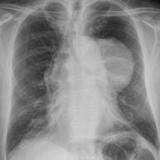

Case 8a Thymoma PA

Date: 03/27/2009

Views: 9543